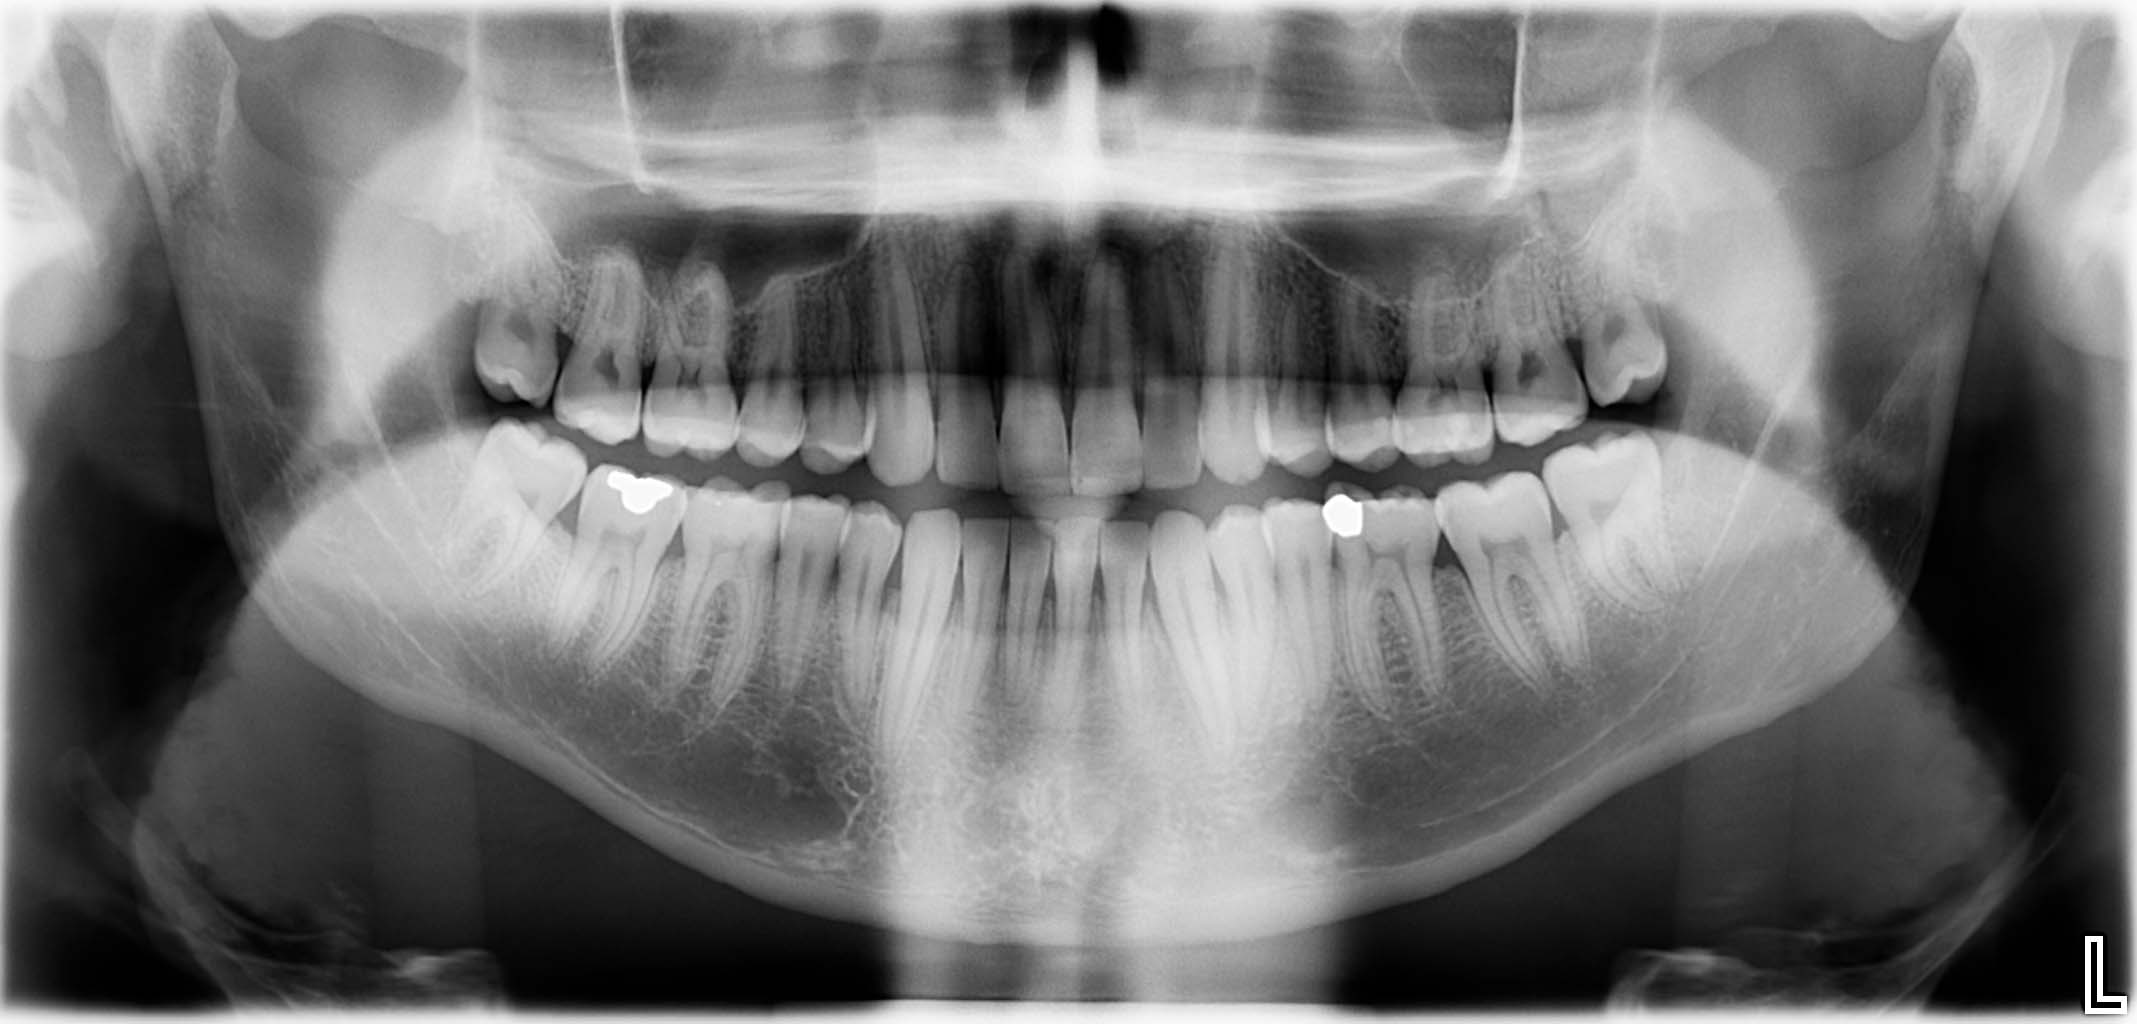

Erfolgreich implantierte Patientenfälle (klinische Fotos)